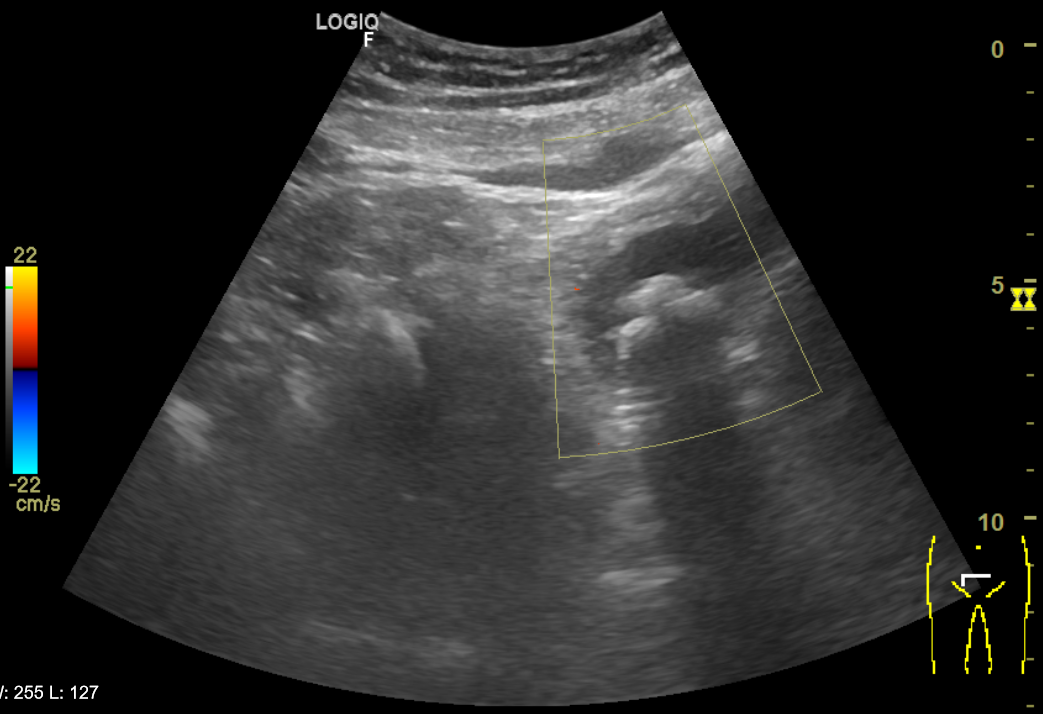

Riñones de morfología y tamaño normales. No se aprecian colecciones intrarrenales ni perirrenales. Sin ectasia de sistemas excretores. Quiste cortical simple en polo superior de riñón izquierdo de 6x6cm. Vejiga poco replecionada de paredes uniformemente engrosadas y trabeculadas. Múltiples imágenes hiperecogénicas con ausencia de registro Doppler y con sombra posterior que sugiere cistolitiasis. Próstata de aspecto normal con volumen de 21 cc. Volumen premiccional de 89 cc y posmiccional de 11 cc.